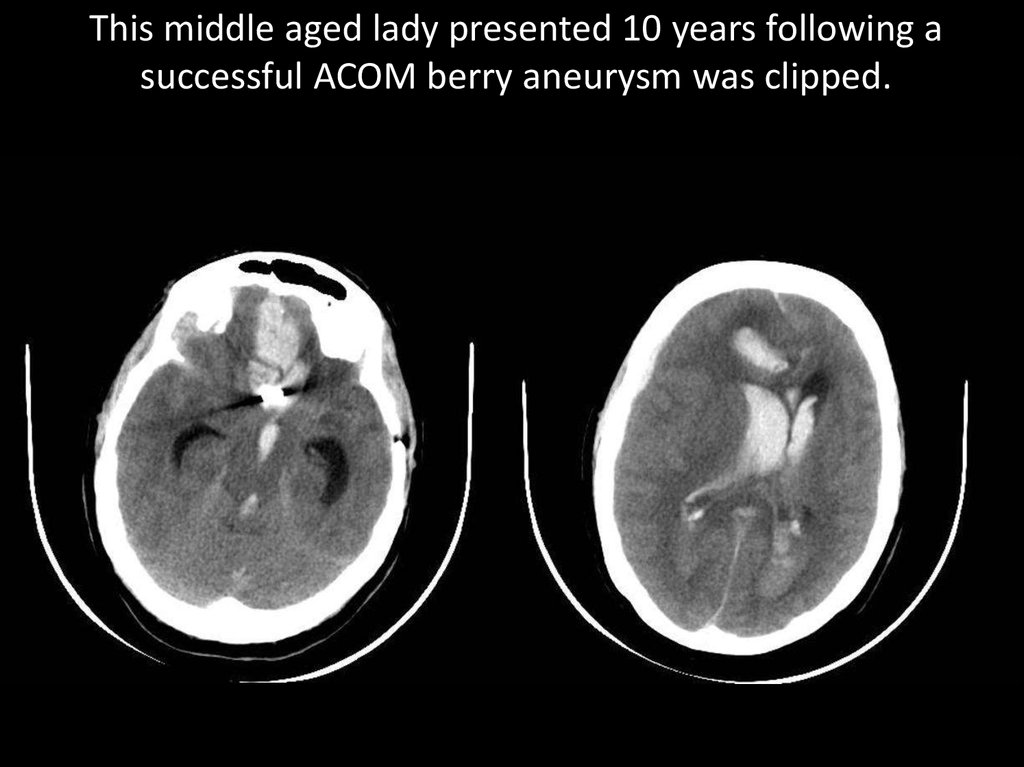

This middle aged lady presented 10 years following a

successful ACOM berry aneurysm was clipped.